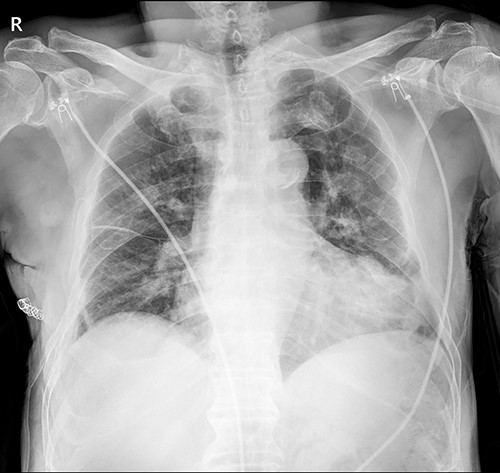

On 25 November 2021, a 68-year-old male, a victim of a motor vehicle accident, presented with multiple rib fractures and hemopneumothorax in the right hemithorax. On hospital Day 2, oxygen saturation gradually dropped under 90% despite proper support, and the patient’s right chest wall showed a newly occurred flail motion. We decided to stabilize rib fractures emergently. The operation was performed routinely, with bicortical screw fixation after exploration of the thoracic cavity. There were no specific intraoperative or postoperative events, and the patient was safely discharged from the hospital with stitches removed on hospital Day 17 (Fig. 1.).

Immediate postoperative chest X-ray after plates removal (24 February 2022).